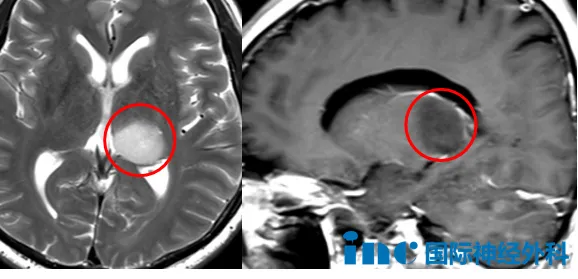

2025年4月,他因体检发现脑部占位,伴随记忆力减退。进一步检查提示左侧丘脑-海马尾部有一个23x19x20mm的占位,低级别胶质瘤可能性大,医院建议手术。可一想到开颅,王先生退却了——他转而尝试中药调理,惊喜地发现记忆力似乎回来了。

可疾病的轨迹并未如人所愿,8个月后的复查结果显示,病灶已增大至24x20x25mm。肿瘤在静默中生长,也再次将那个沉重的问题推到他面前——手术,还是不手术?

巴教授仔细评估后指出,虽然影像学特征偏向低级别胶质瘤,但病灶中已出现强化信号,提示存在恶性转化可能,不宜继续等待。手术不仅可以明确诊断,还可以尽可能切除肿瘤。现在手术,比出现严重症状后再手术,恢复更快、效果更好。

针对王先生最关心的手术风险,巴教授也给予了精准剖析:肿瘤位于丘脑,术后可能存在右侧运动功能影响的风险,但很低。他还分享了不久前在苏州完成的一例类似位置手术,患儿术后并未出现偏瘫,这给了王先生更多信心。王先生他决定不再等待,主动寻求巴教授下周在华期间的示范手术机会。